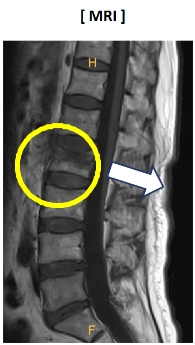

우선 의심되는 부위의 척추체를 중심으로 X-ray를 촬영합니다. 척추 압박골절은 다른 부위처럼 뼈가 갈라지거나 벌어지지 않고, 진단명과 같이 골절된 척추체가 압박되어 찌그러지는 변형을 보입니다. X-ray상 척추체가 찌그러진 모습이 보이면, MRI 촬영을 하여 골절된 부위가 급성 혹은 과거 골절인지 판명하게 됩니다. 때에 따라서는 CT 촬영으로 판단하기도 합니다. 또한 골밀도 검사(BMD)를 하여, 골다공증 유무를 확인 후 종합적으로 추후 치료에 대해서 판단합니다.